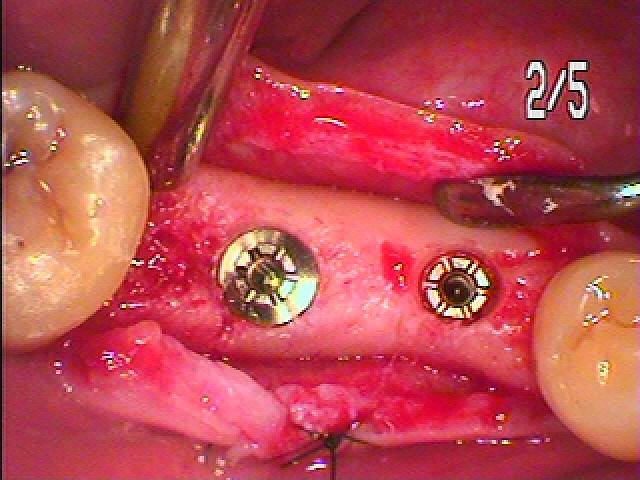

右下のインプラント治療 2本埋入|お知らせ |広島市安佐南区の歯科医院 右下のインプラント治療 2本埋入 トップ お知らせ・ブログ お知らせ 右下のインプラント治療 2本埋入 右下のインプラント治療 2本埋入 右下、5,6番にインプラントを埋入していきます 口腔内はこんな状態です 残根が認められます このように埋入しています 埋入時になります 骨の形態もいいです 縫合して終了となります 仮歯にて歯肉形態を付与していきます 歯肉形態を作った上にてセラミックにて上部構造を作成していきます 最終補綴時のレントゲンになります Web診療予約 初めての方へ 選ばれ続ける理由 院内設備について 歯が痛いしみる一般歯科 歯がぐらぐらする歯周病 健康な歯を保ちたい予防歯科 子供の虫歯予防をしたい小児歯科 銀歯をセラミックに審美歯科 白い歯を目指しませんか?ホワイトニング 矯正専門医がいるので安心矯正歯科 抜けた歯を補いたいインプラント・入れ歯 医院案内 スタッフ紹介 メリィハウス歯科クリニックオフィシャルホームページ ラベンダー歯科クリニックオフィシャルホームページ お知らせ・ブログ ホーム 診療科目 一般歯科 歯周病治療 予防治療 小児歯科 審美治療 ホワイトニング 矯正歯科 入れ歯・インプラント マウスピース矯正 初めての方へ 院長・スタッフ 設備紹介 医院案内・アクセス メニューを閉じる